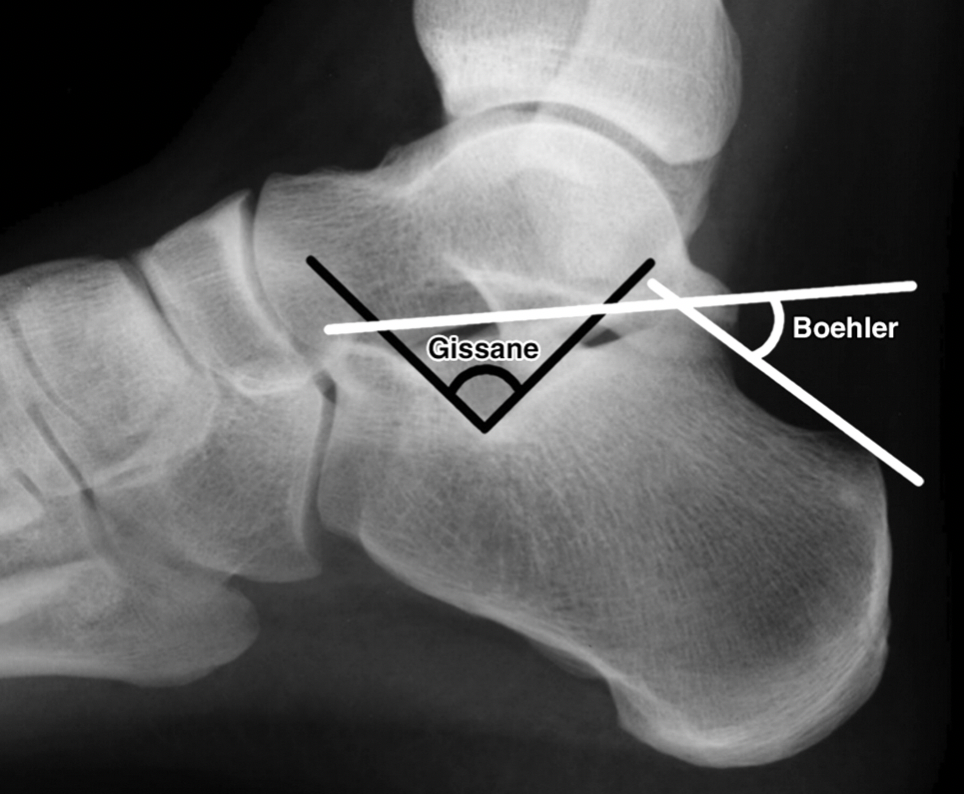

X voet lateraal: (Zie foto)

- Hoek van Böhler: normaal 25°-40°, een afname in de hoek is verdacht voor fracturen

- 1e lijn: bovenste rand tuberositas posterior calcaneus naar apex achterste deel articulus subtalaris

- 2e lijn: apex achterste deel articulus subtalaris naar processus anterior van de calcaneus

- Critical angle of Gissane: 100°-130°, een toename in de hoek is verdacht voor fracturen

- 1e lijn langs bovenste aspect van posterior facet

- 2e lijn langs bovenste aspect van anterior facet